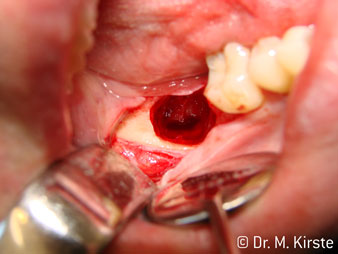

La scelta dell'angolo di 45° del contrangolo offre numerosi vantaggi in sede di utilizzo. I colleghi chirurghi, per i quali è stato messo a punto in primo luogo il contrangolo, noteranno in fretta la possibilità di lavorare in modo molto mirato. In particolare, durante l'estrazione dei denti del giudizio (Fig. 2), non sono necessarie estese resezioni del tessuto molle nell'area della guancia (Fig. 3). La forma della testina del contrangolo, insieme a lievi rotazioni della stessa durante la preparazione, permettono di lavorare in modo rapido e sicuro nella regione retromolare.

Fig. 3